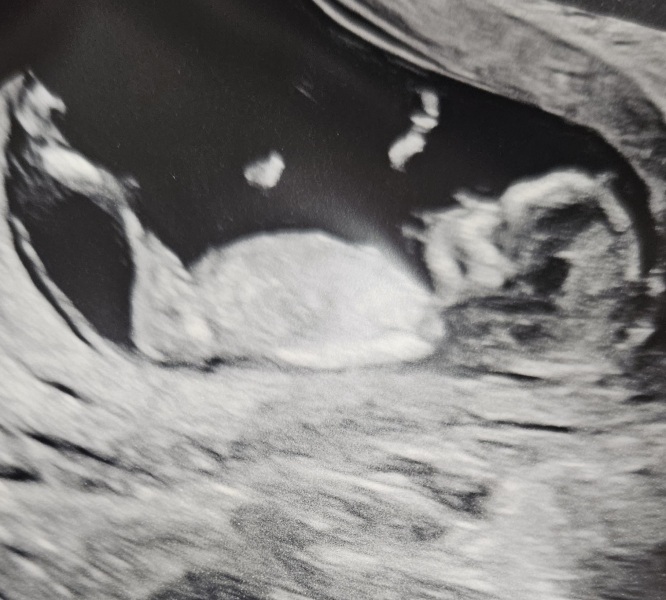

All is well 🥰 baby measuring bang on 13+1 and due 4th November. It was being very awkward and didn't want to move so I was scanned whilst laying on my side and it finally stretched out 🥰 looks super long 🤣

They really do look so long on that scan photo 😂

@Westy22 that’s amazing news. What a great scan pic too 🥰 So mad to think all that growing and stretching is going right now inside and you can’t feel it!

@Westy22 aw lovely news 🥰 What a great scan pic too! They look super chilled and comfy in there 😄💗

@Westy22 he/she looks so much 'older' than 13wks! Are you going to wait till your 20wk one for the gender or do a private one at 15 🙂 lol

Thank you guys 🥰 I panicked a bit when I posted the pic, I hope it didn't trigger anything with anyone. I got lost in the moment 🙈

@jt130593 lol I couldn't believe the legs 🤣 definitely taking after dad with those, feel like it looks long in general tho, I have a long body too so totally makes sense lol

@xxcxdonxx I find it bizarre that it looks like that and I can't feel anything yet. Those long legs are definitely going to let me know it's there soon enough 🤣

@SnookyPook it was very comfy, the amount of shaking I had to do because it didn't want to budge was quite funny thought she was gonna make me start star jumping 🤣🙈

@Supertrooper101 do you think? Maybe because its so stretched out lol we're not finding out , however there is another pic where I feel the nub would indicate its a boy 🤣 my sis is trying to make me find out secretly but I can't do that lol

@Westy22 Awww that's a great scan pic, they really does look quite long, I reckon you'll definitely feel kicks early 😉

@Westy22 what a beautiful scan! Actually made me laugh how chilled and spread out they are hahahha. Im voting boy too! We didn't find out with my son was a lovely surprise!! Xx